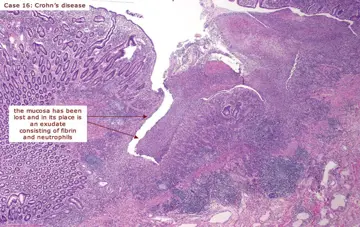

پیشگیری‌از فیبروز در کرون